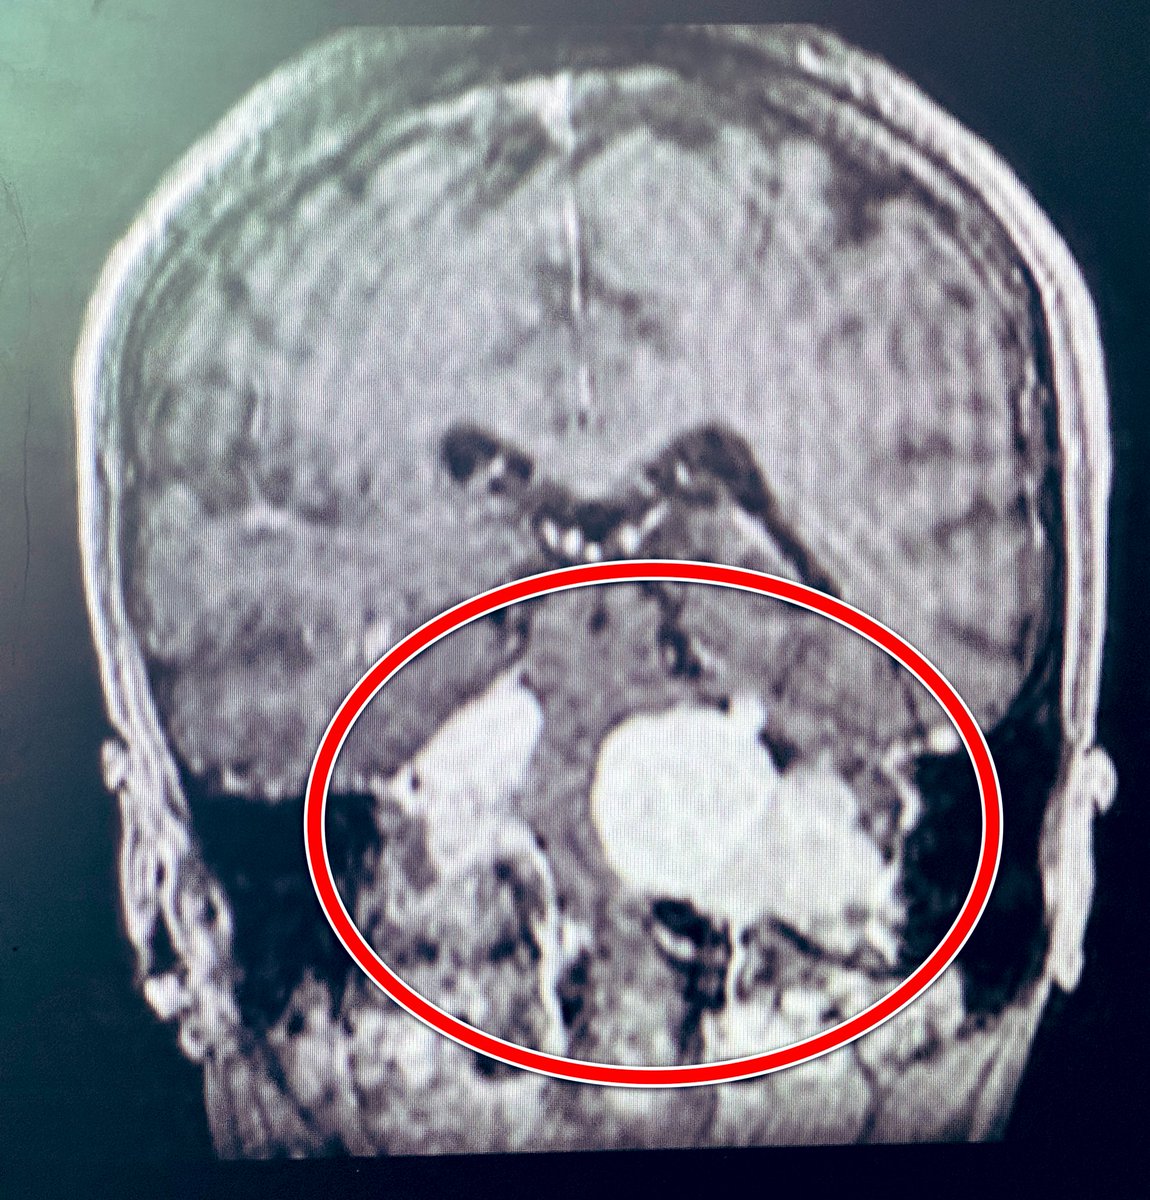

2️⃣جميعهم اعتذر عن اجراء العملية لخطورتها على حياته

براك وصل لمرحة لا يستطيع الوقوف ولا البلع وبالكاد يتنفس

قالوا لوالده:خذ ابنك ليتوفى بين أسرته وأحبته!

بعد أسبوعين من اجراء العملية في @HMG بريدة

براك يتماثل تدريجيا للشفاء بفضل الله